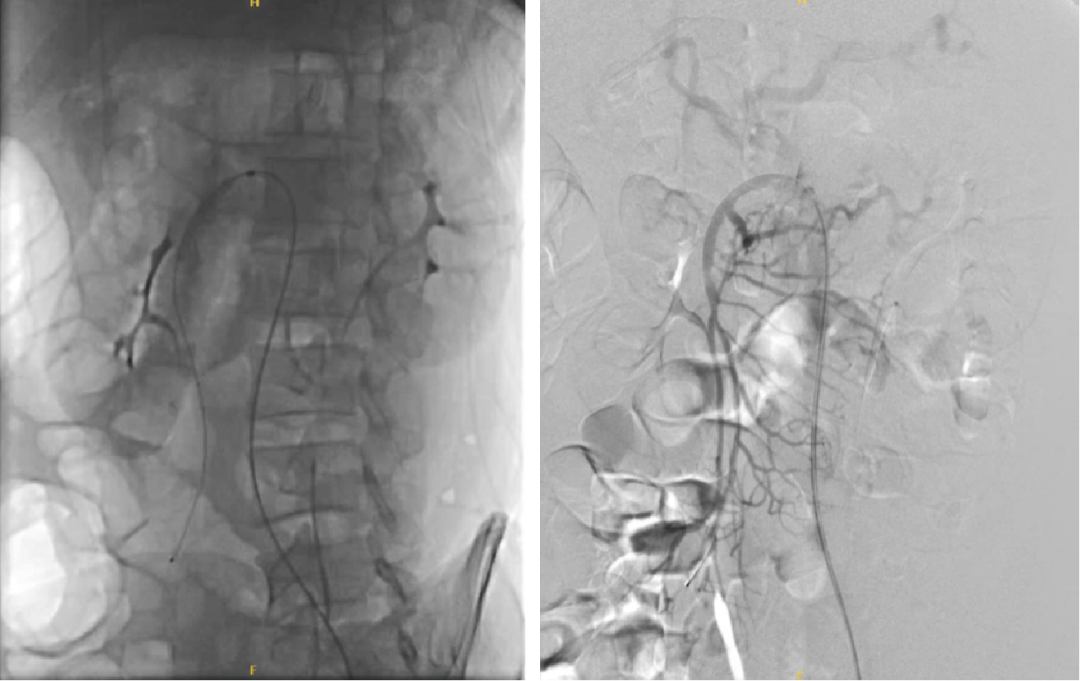

通过下面4个具体病例进一步说明TEVAR在治疗复杂型B型主动脉夹层中的治疗原则、注意事项及应用。

34岁男性,SMI灌注不良,TEVAR后SMA重建

48岁男性,胸腹痛20小时,右下肢一过性麻木,TEVAR治疗

夹层累及股动脉(支架入路),需要参考术前CT,在彩超引导下穿刺入真腔,或者行股动脉剖开,直视下辨认真假腔。

术后处理:TEVAR后仍需关注脏器缺血等问题,必要时对分支血管进行进一步处理。